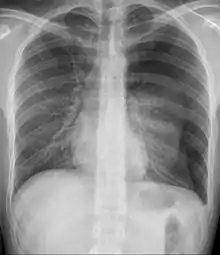

- Pneumothorax